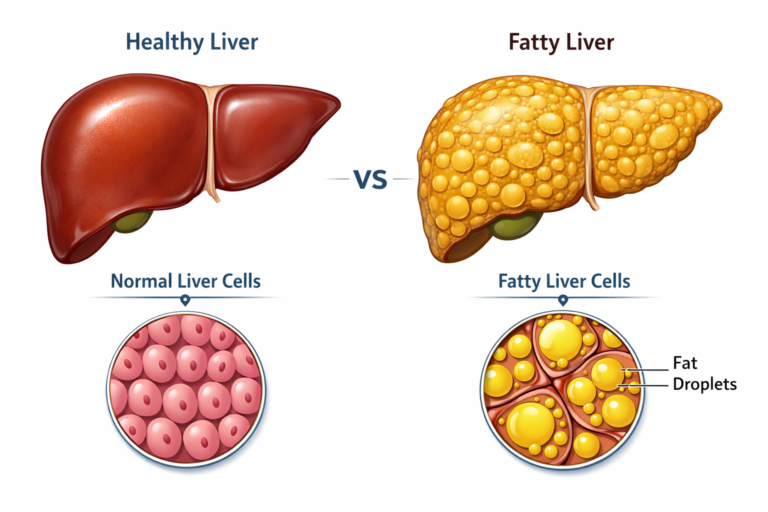

Looking for Hepatitis C treatment in Hyderabad? Dr Rahul Dubbaka offers advanced antiviral therapy with 95%+ cure rates at People’s Hospital, Pragathi Nagar. Book your consultation today at +91 9100921514. Hepatitis C is a viral infection that primarily affects the liver and can silently damage it over time. If left untreated, it may lead to serious complications such as cirrhosis, liver failure, and even liver cancer. The good news is that with modern medical advancements, Hepatitis C is now highly curable with effective antiviral medications.

Hepatitis C is caused by the Hepatitis C virus (HCV). It spreads mainly through contact with infected blood. Many people with Hepatitis C do not experience noticeable symptoms initially, which is why the infection often remains undiagnosed for years.

Over time, chronic Hepatitis C can cause progressive liver inflammation, leading to fibrosis (scarring), cirrhosis, and increased risk of liver cancer.

Complications of Untreated Hepatitis C

If not treated, Hepatitis C may lead to:

Liver cirrhosis

Liver failure

Portal hypertension

Ascites

Liver cancer (Hepatocellular carcinoma)

Early treatment prevents these complications and improves life expectancy.